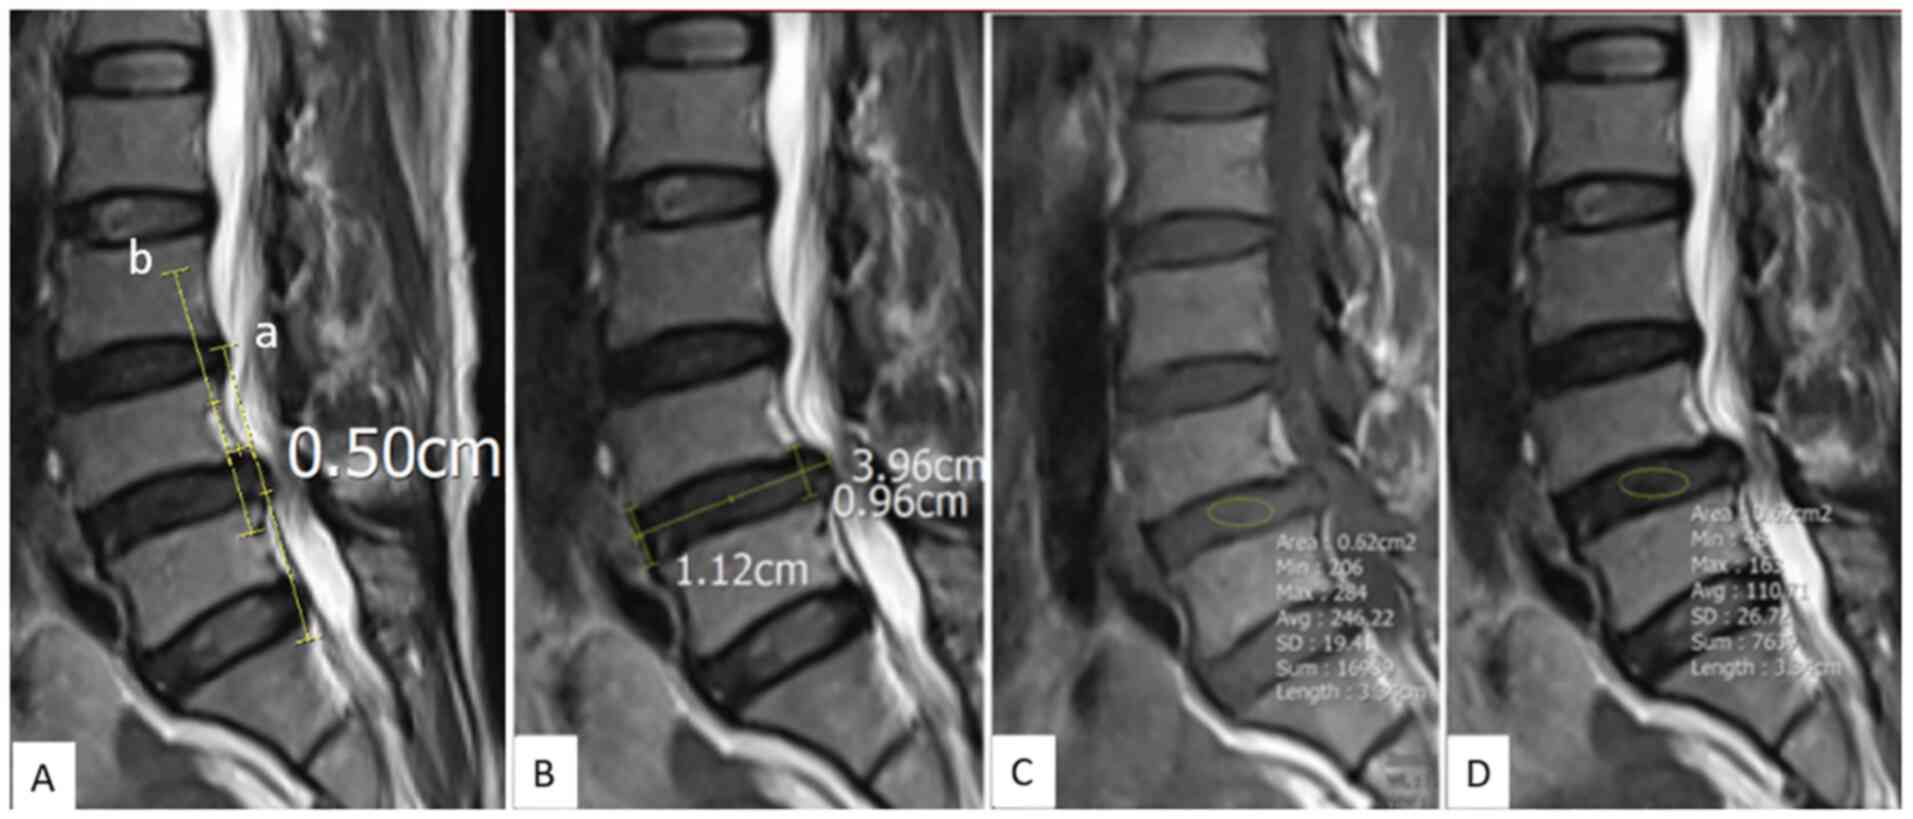

Figure 2

Representative measurements from one patient. (A) Sagittal T2W images. The Tailliard method was used to measure the slip distance. (B) Sagittal T2W image. The Farfan Index was used to calculate disk height. Farfan Index=(anterior disk height-posterior disk height)/disk width. (C) Sagittal T1W image and (D) Sagittal T2W image. Regions of interest were placed in the center of the disks and the minimum, maximum, and mean signal values were obtained. T1W, T1-weighted; T2W, T2-weighted.

The disk height was determined by calculating the Farfan Index, as the sum of the anterior and posterior border heights divided by the disk width as measured on the sagittal plane of T2W images (Fig. 2) (16). Facet fluid was measured perpendicular to the joint at the site of greatest volume on axial T2W images (Fig. 3) (17,18). The ligamentum flavum was measured at the joint surface level on axial T2W images (Fig. 3) (19). Quantitative values for disk signal, including minimum, maximum, and mean signal values, were obtained by placing a region of interest (ROI) ellipse in the center of the intervertebral disk on sagittal T1W and T2W images (Fig. 2).